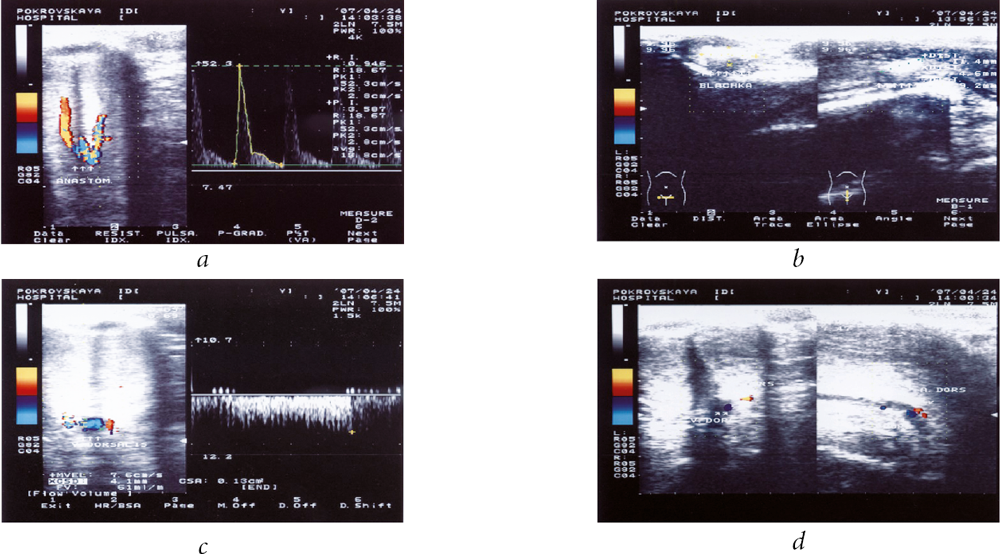

In performing ultrasound dopplerography on the penis, vascular changes were detected in 16 of the 27 patients examined, and 8 patients (50%) had manifestative venogenic compensated and subcompensated erectile dysfunction (Figures 2 and 3). The remaining 11 patients had no signs of vascular changes (Table 1).

Fig. 2. Ultrasound dopplerography of the penis of Patient D (36 years old with Peyronie’s disease and venogenic erectile dysfunction): a) in the distal part of the penis, the plaques are from 1–2 to 8.5 mm; b) the dorsal vein did not collapse, and blood flow along it was 30 ml/min. Valsalva test was positive

Fig. 3. Ultrasound dopplerography of the penis of Patient T (55 years old with Peyronie’s disease and venogenic erectile dysfunction). The patient has Dupuytren’s contracture: a) abnormality of the structure of the cavernous arteries, i.e., anastomosis of the cavernous arteries in the crus of the penis; b) plaques in the cavernous bodies (plaque of 11.4 mm × 4.6 mm × 9.2 mm is marked), which deformed the penis; c) and d) noncollapse concurrence of the dorsal vein as a sign of venous erectile dysfunction